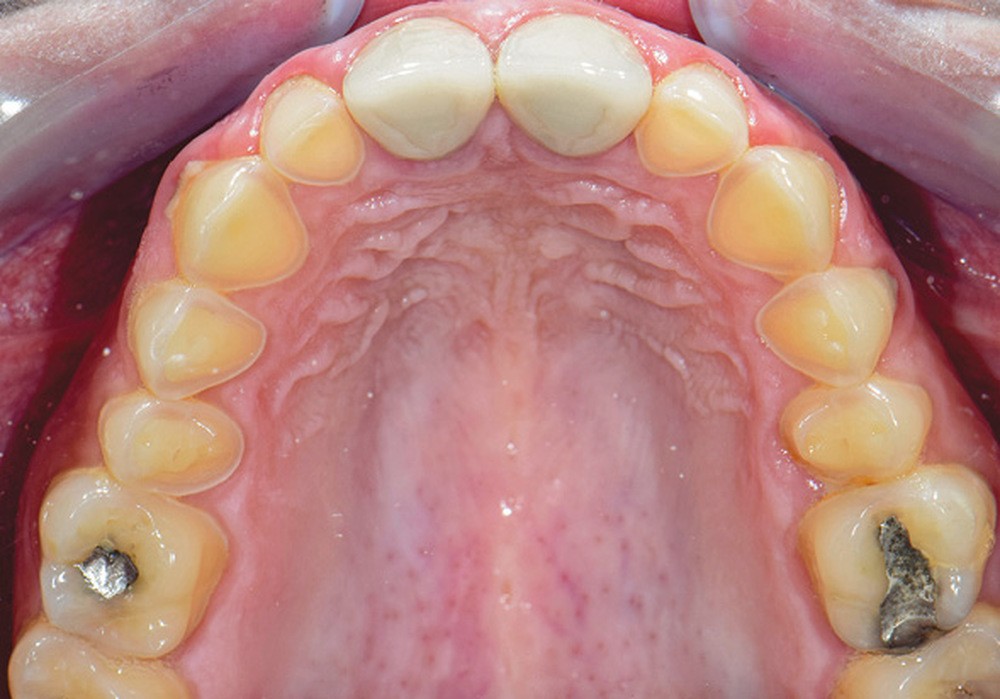

L’arcade maxillaire présente des signes d’usure érosive caractéristiques d’attaques acides : surface lisse, de couleur satinée, présence d’un pourtour d’émail sain en regard du sulcus, et effacement des morphologies dentaires telles que la disparition des cuspides palatines des prémolaires et de la 16. En revanche, 26 et 46 ne présentent aucun problème d’usure. La patiente ne rapporte pas de signes d’hyperesthésie dentinaire. Par ailleurs, la dimension verticale d’occlusion (DVO) étant conservée, la patiente présente une usure majeure compensée par l’égression dentaire (ce qui montre une évolutivité lente).